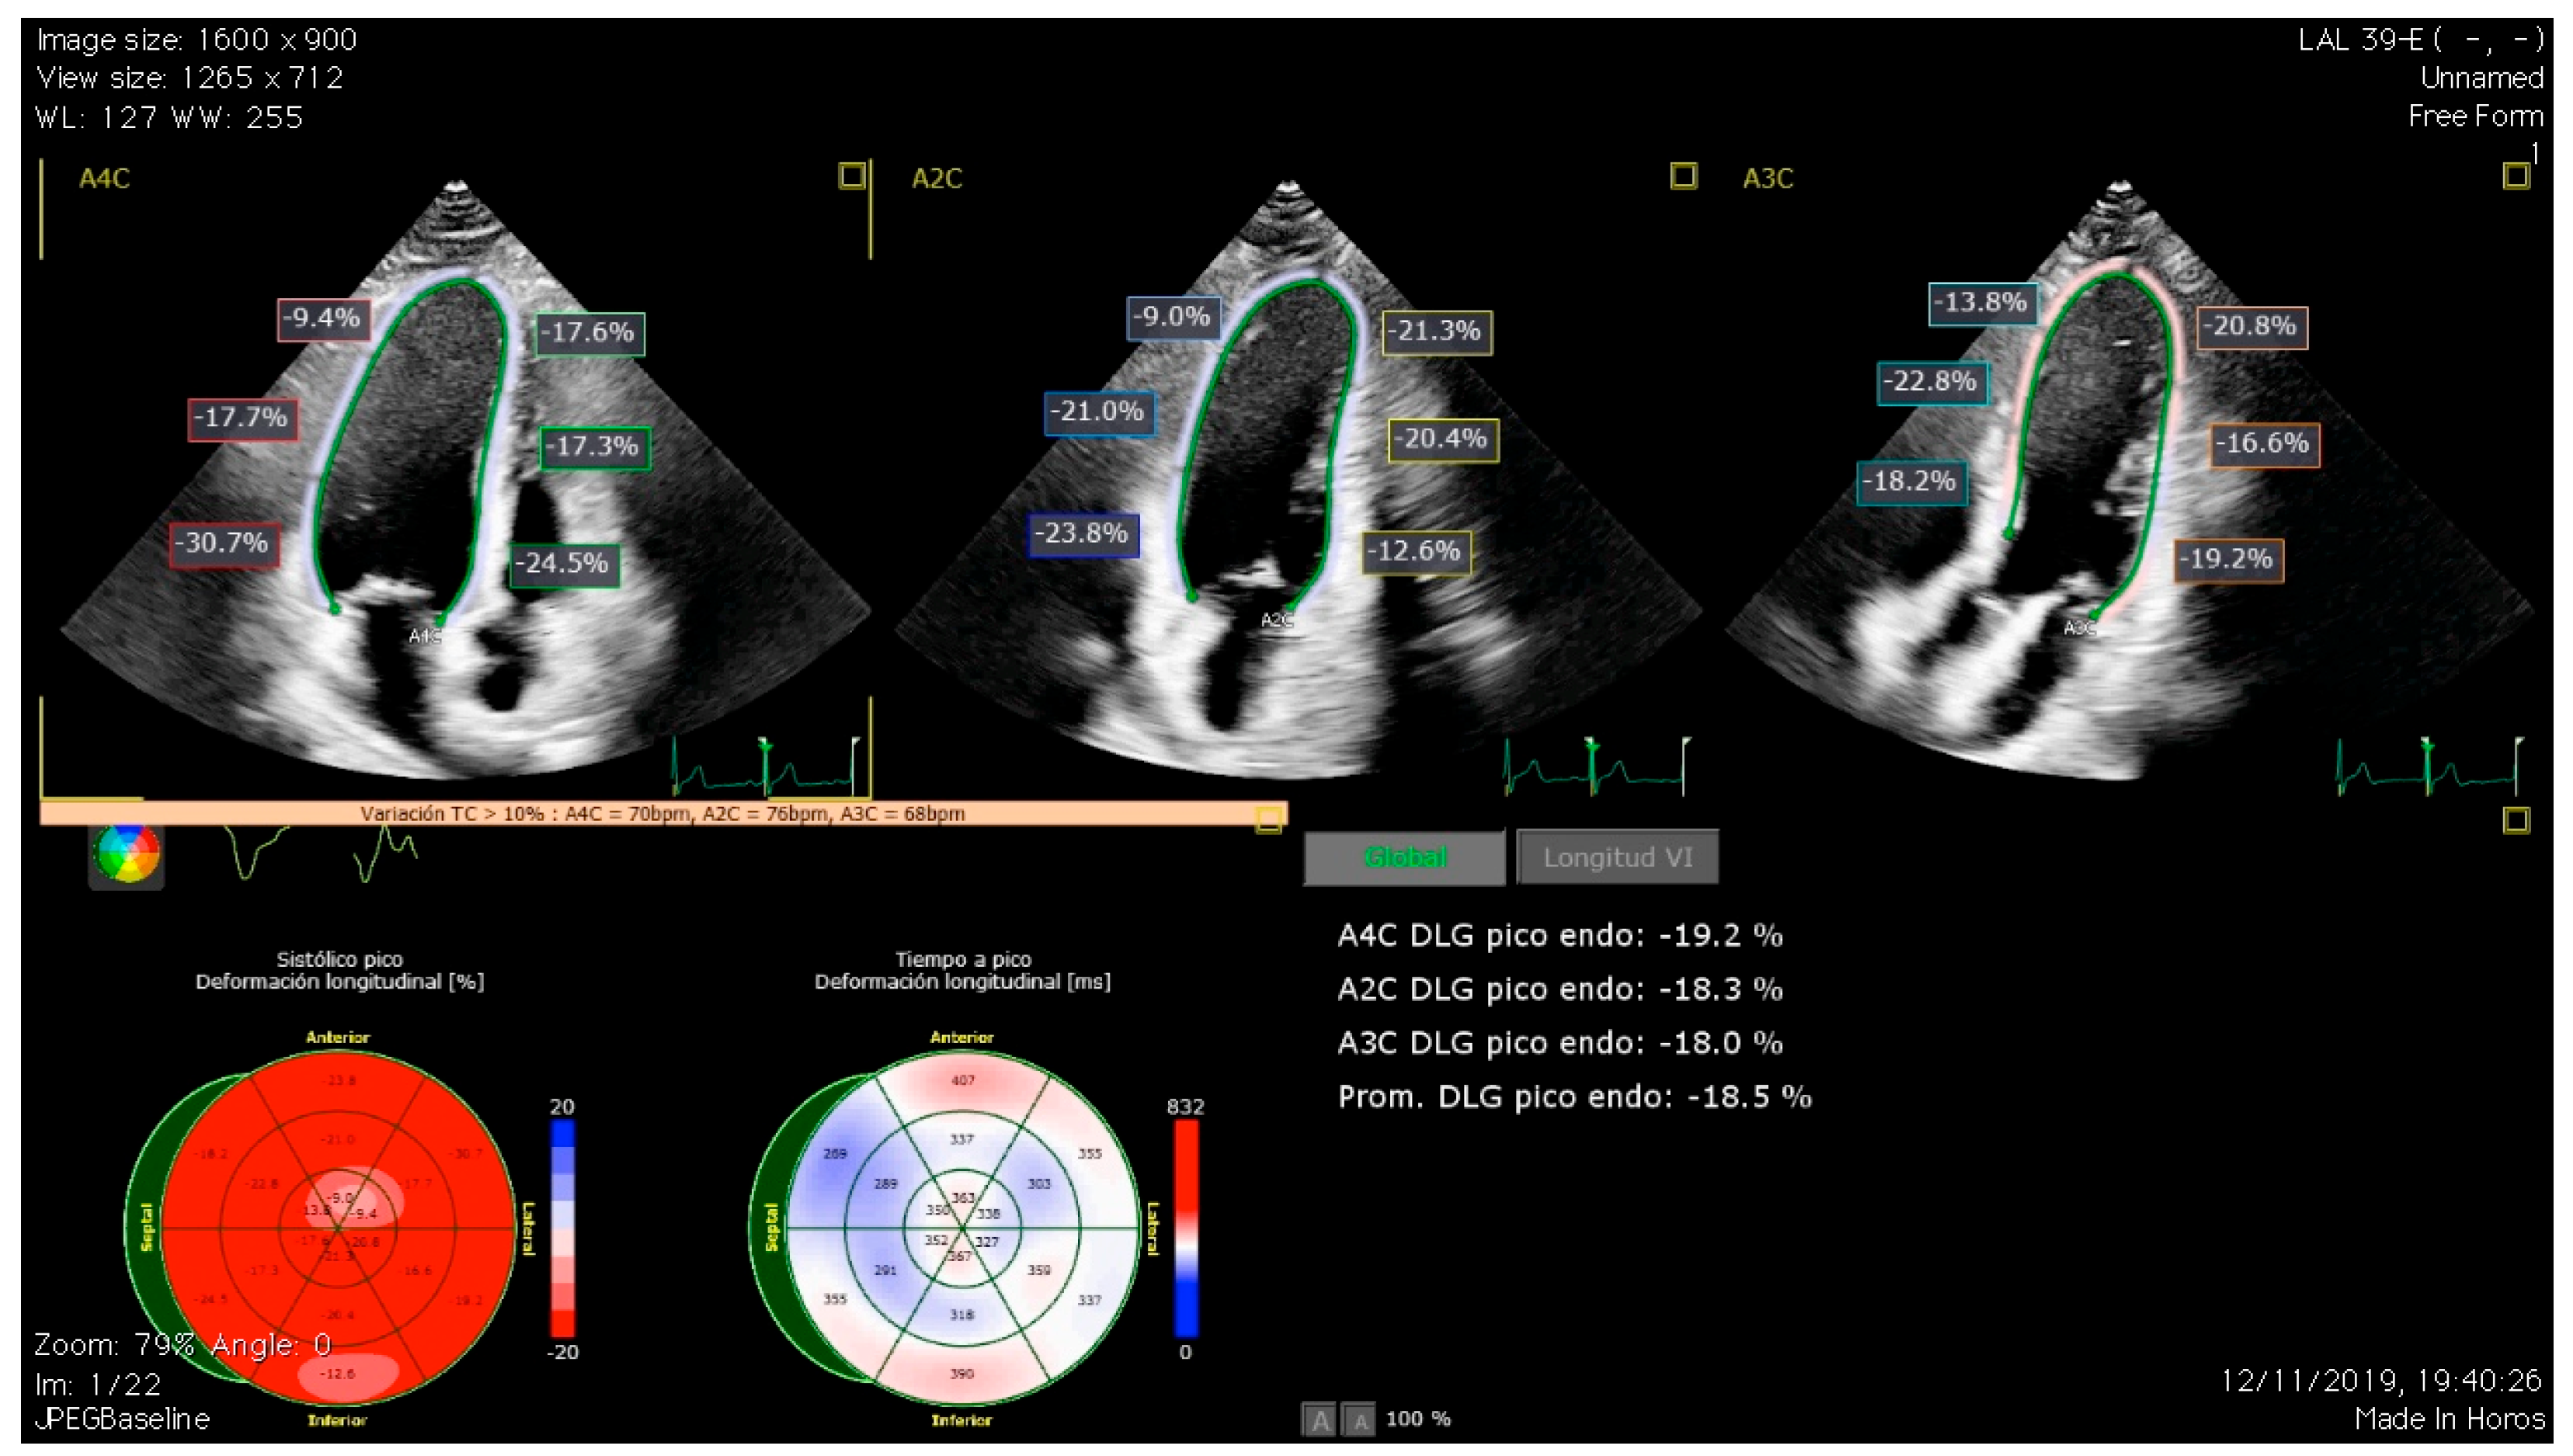

3.1. Global Longitudinal Strain